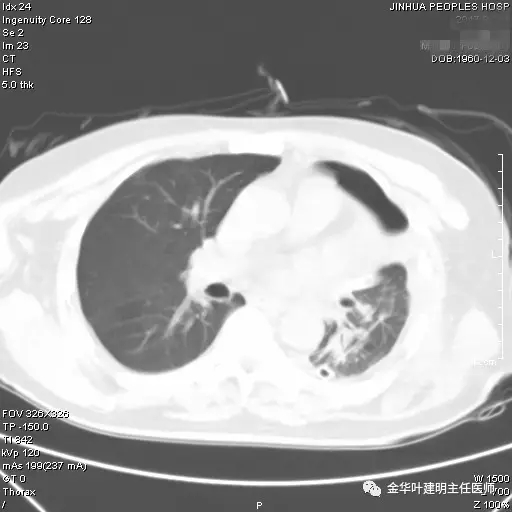

图一:红色箭头所指处示左肺上叶开口处的病灶,不仔细看根本发现不了,也极易漏掉

图二示:纵隔窗左肺上叶开口处新生物,相对肺窗稍明显